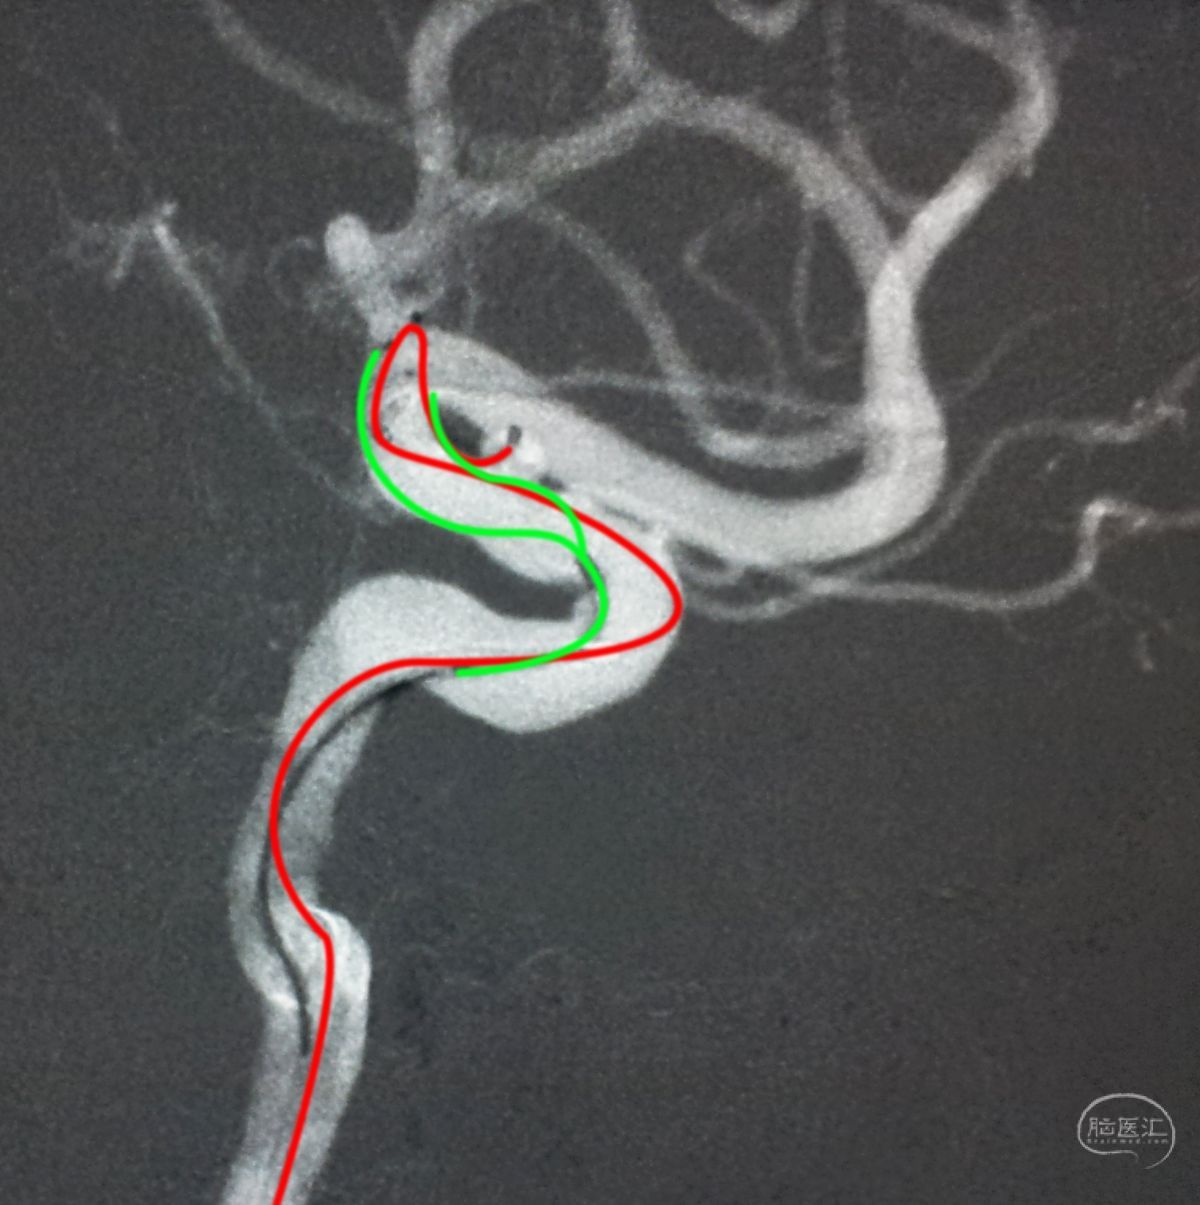

跨瘤颈释放Solitaire 4×20支架(蓝线),压住微导管(红线),在支架保护下经返折的微导管送入弹簧圈填塞瘤腔。

依次送入QC-2-4-3D,2-3-Helix,1.5-2-Helix,1.5-2-Helix四枚弹簧圈,最后一枚弹簧圈将管头(箭头)顶出瘤腔。

将Traxcess 14微导丝送入微导管,稍向远心端送微导管,使管头远离动脉瘤,再缓慢撤离。